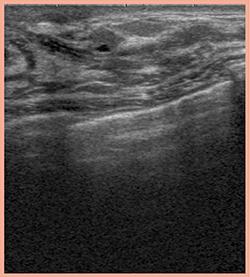

図1に,超音波で描出された乳腺の正常構造の画像を示す。中心の高エコーライン,等エコー模様,高エコー域というのは乳腺の共通の構造であり,小葉と乳管の周囲の膠原線維の密な間質(周囲間質)が等エコーとして,また,浮腫状で膠原線維の疎な間質(浮腫状間質)は高エコーとして描出される。周囲間質の分布が不均等な場合や超音波の分解能が足りない場合は等エコー構造物が途切れて見えるが,中心では必ず小葉と乳管につながっている。

図1 超音波における乳腺の正常構造の描出